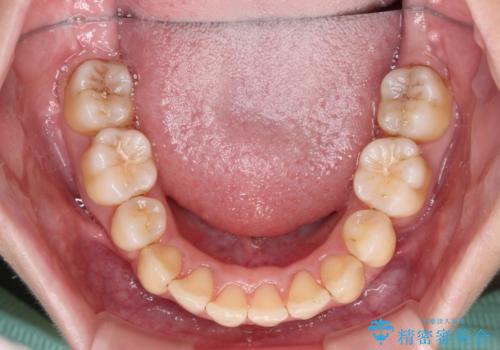

変則的な歯列であったため、奥歯がしっかりと咬み合うのか、前歯はしっかりと排列できるのかと不安ではありましたが、結果としてはきれいに整った歯列にて終了することができました。